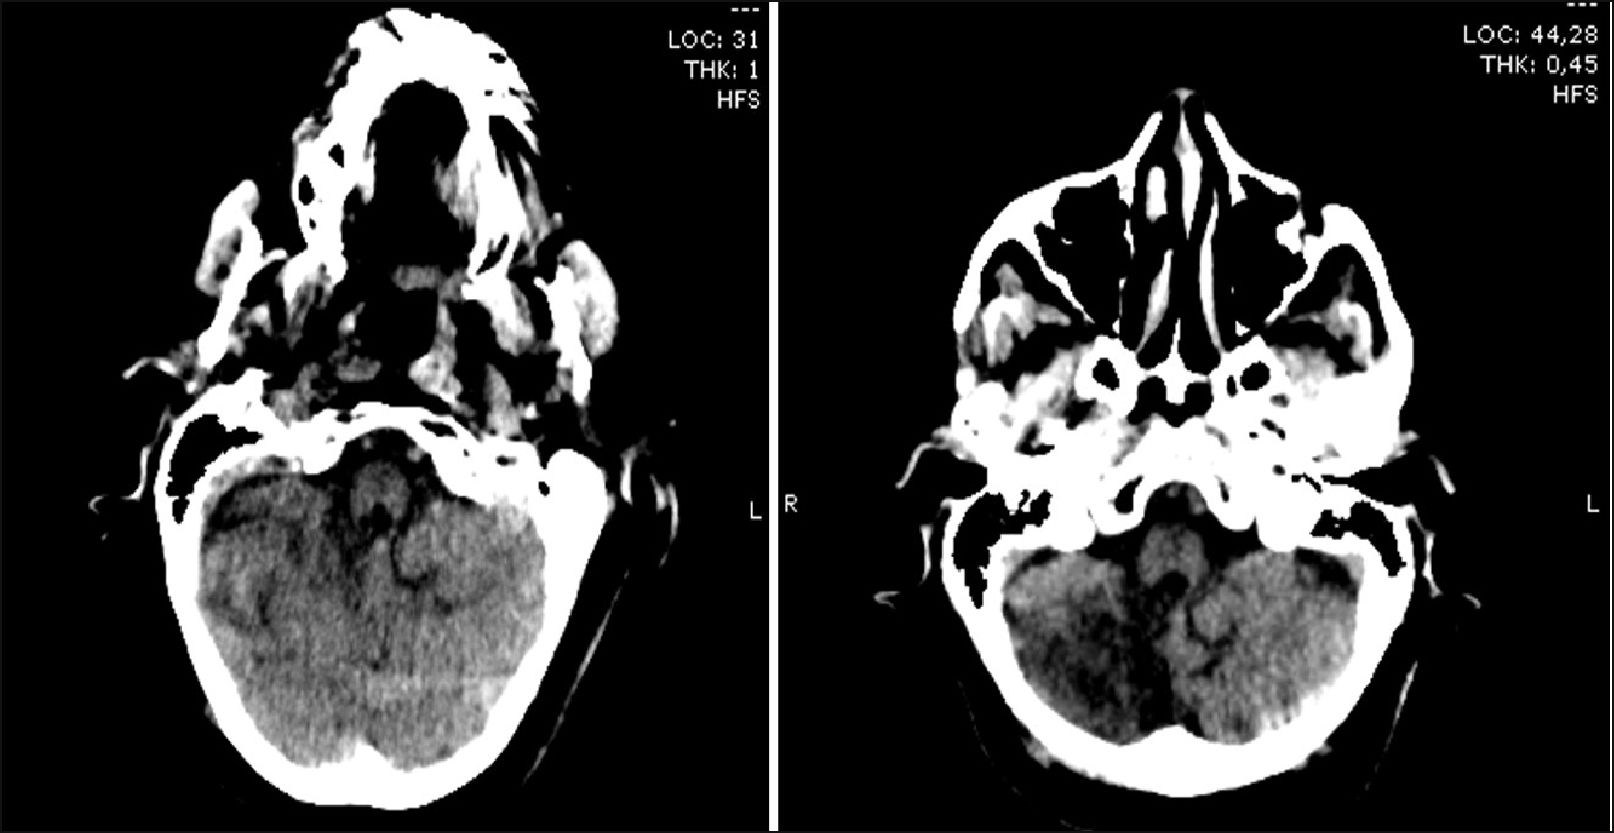

Paciente femenina de 64 años de edad con antecedentes de hipertensión arterial, tabaquismo, enfermedad renal crónica, accidente cerebro vascular (ACV) isquémico sin secuelas un año previo a la consulta. Es traída a emergencias por cuadro consistente en afasia de expresión y hemiparesia facio-braquio-crural izquierda de menos de tres horas de evolución. Ingresa estable, con glucemia capilar de 118mg/dl, afebril. Se encontraba alerta, pupilas reactivas isocóricas, desviación conjugada de la mirada a la derecha, cumplía órdenes simples, presentaba hemiparesia facial severa, braquial severa y crural moderada izquierda. Ruidos cardiacos hipofonéticos, sin signos de falla cardiaca aguda. Se calcula NIHSS (National Institute of Health Stroke Scale) de ingreso:17. Se realiza tomografía (TC) de cerebro (Figura 1) sin signos de sangrado agudo, se interpreta ACV isquémico en ventana terapéutica. Se realiza electrocardiograma que evidencia elevación del segmento ST en cara antero-inferior (Figura 2), por lo que es evaluada por cardiología y se decide trombolísis con activador del plasminoógeno tisular recombinante (rTPA) (tiempo puerta aguja: 3,5hs).

Evoluciona a los 40 minutos después del inicio de rTPA con disminución del estado de alerta y somnolencia, por lo que se suspende trombolítico, se realiza nueva tomografía de cerebro (Figura 1) con hipodensidad difusa en hemicerebelo derecho (ya presente en tomografía cerebral previa), y nuevo electrocardiograma (Figura 2) con persistencia de elevación del segmento ST siendo menos significativa. Posteriormente profundiza el deterioro del sensorio con requerimiento de intubación orotraqueal, ventilación mecánica invasiva y traslado a unidad de terapia intensiva, se realiza angiotomografía de cerebro (Figura 3) informándose hipodensidad del parénquima cerebral derecho con pérdida de la diferenciación entre la sustancia gris y blanca a predominio parieto-temporo-occipital de aspecto isquémico, además de áreas densas a nivel del centro semioval izquierdo que se extienden hacia la región pericallosa compatibles con sangrado asociado a volcado ventricular homolateral. No se observa flujo del segmento M1 de la arteria cerebral media derecha.